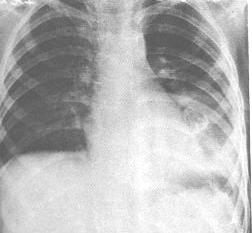

| 纵隔畸胎瘤。胸片正位(上图)示肿瘤凸入于左下肺野,于第三前肋间可见肿瘤内的骨化影。侧位(下图)示肿瘤位于后纵隔下部,轮廓较清楚,肿瘤的前上部及下部均可见骨化影。该病例的位置少见。

1.X线表现: ①纵隔向一侧增宽,形成肿块。边缘多光滑、整齐。 ②肿瘤由不同组织构成,密度可不甚均匀,囊性者密度低而均匀。 ③若于肿瘤中发现骨骼、牙齿或钙化则为特异性X线征。 ④侧位上位前纵隔,主要在胸骨体后方。 ⑤透视下,利用胸腔压力变化,对鉴别囊性或实体性有帮助。 ⑥肿瘤较大可明显向肺野内突出,且可与支气管相通,易致误诊。 2.CT表现: ①皮样囊肿与囊性畸胎瘤表现为前纵隔内混杂密度肿块,既有低密度脂肪和液体成分、也含软组织密度和/或钙化。肿块边缘光滑、边界清楚。 ②实性畸胎瘤通常为较均一软组织密度肿块,常呈分叶状,与周围结构多分界不清。 3.MRI表现: ①畸胎瘤表现为纵隔内肿块,易发生在前纵隔,偶见于纵隔其他部位,由于内含脂肪、钙化、囊性等多种成分而呈混杂信号。 ②MRI对肿块内钙化确定不及CT,但易于无示肿块与相邻低信号血管结构的关系。 常规胸片检查,前纵隔囊性肿块并含有钙化或牙齿,高度提示囊性畸胎瘤。CT和MRI检查不但能确定肿瘤大小、位置及其与邻近血管结构的关系,且可通过肿块内含有多种密度和信号成分而确诊为囊性畸胎瘤。恶性畸胎瘤定性困难。 |